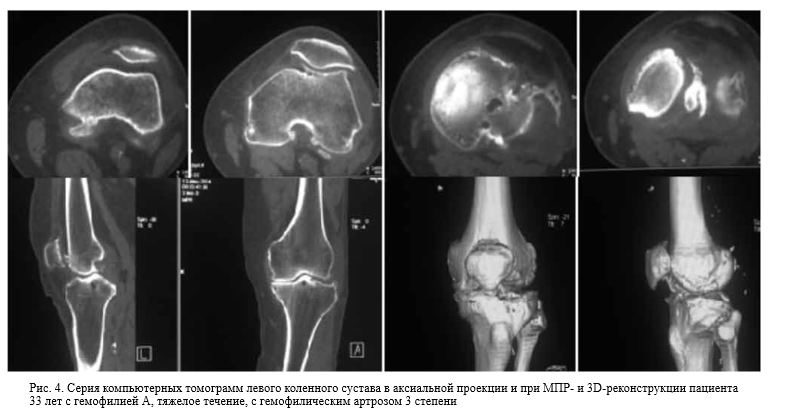

Мрт и кт суставов

Мрт и кт суставов 111 фото